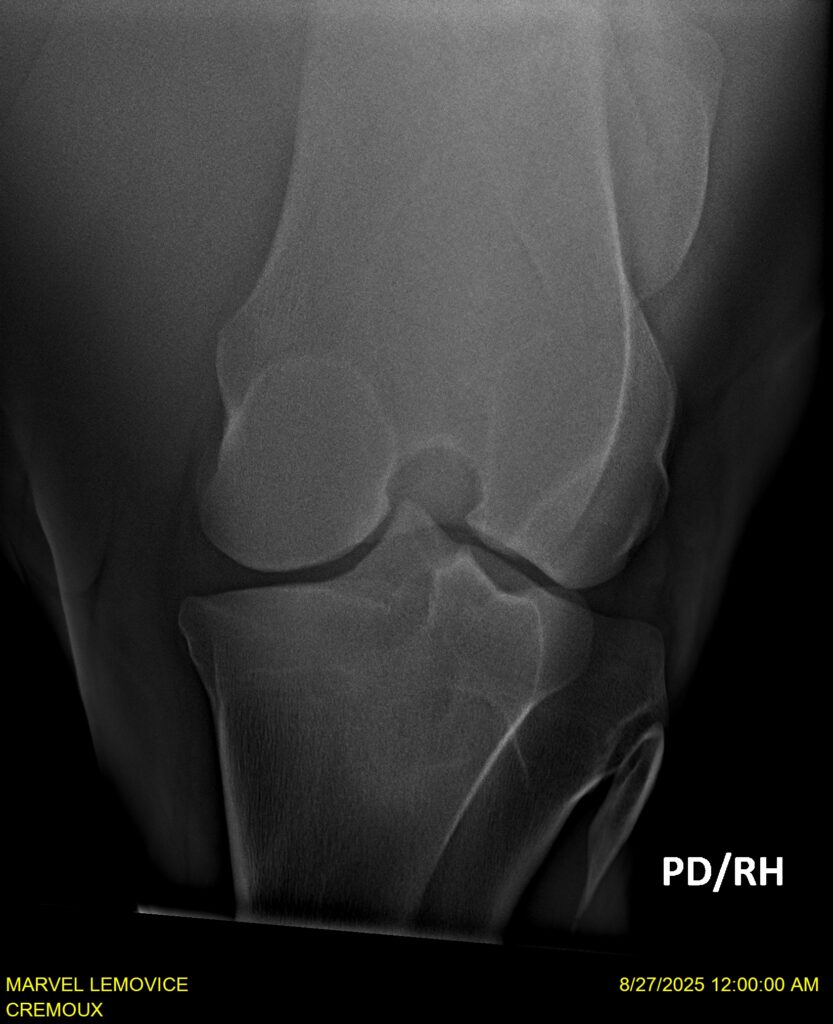

MARVEL LEMOVICE, hongre, Selle Français prend 4 ans en 2026. POPSTAR LOZONAIS x ROSIRE sur une excellente souche maternelle de l’élevage PLATIERE. Débourré aux trois allures et mise en route à l’obstacle. Super modèle avec du cadre et de la force, cheval respectueux avec des moyens. Très agréable au quotidien. Transport OK, maréchalerie OK, santé RAS, Bilan 20 clichés radios + clinique OK.

RADIOS ET CLINIQUE